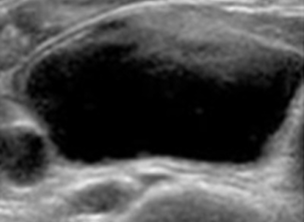

실제 환자의 변화

-

- 치료 전

- 갑상선 낭성 양성 결정

- 1개월 후

- 80% 크기 감소

- 4개월 후

- 95% 크기 감소